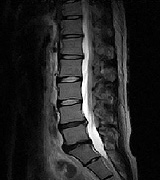

MRI画像

• mri01

• mri02

• mri03

• mri04